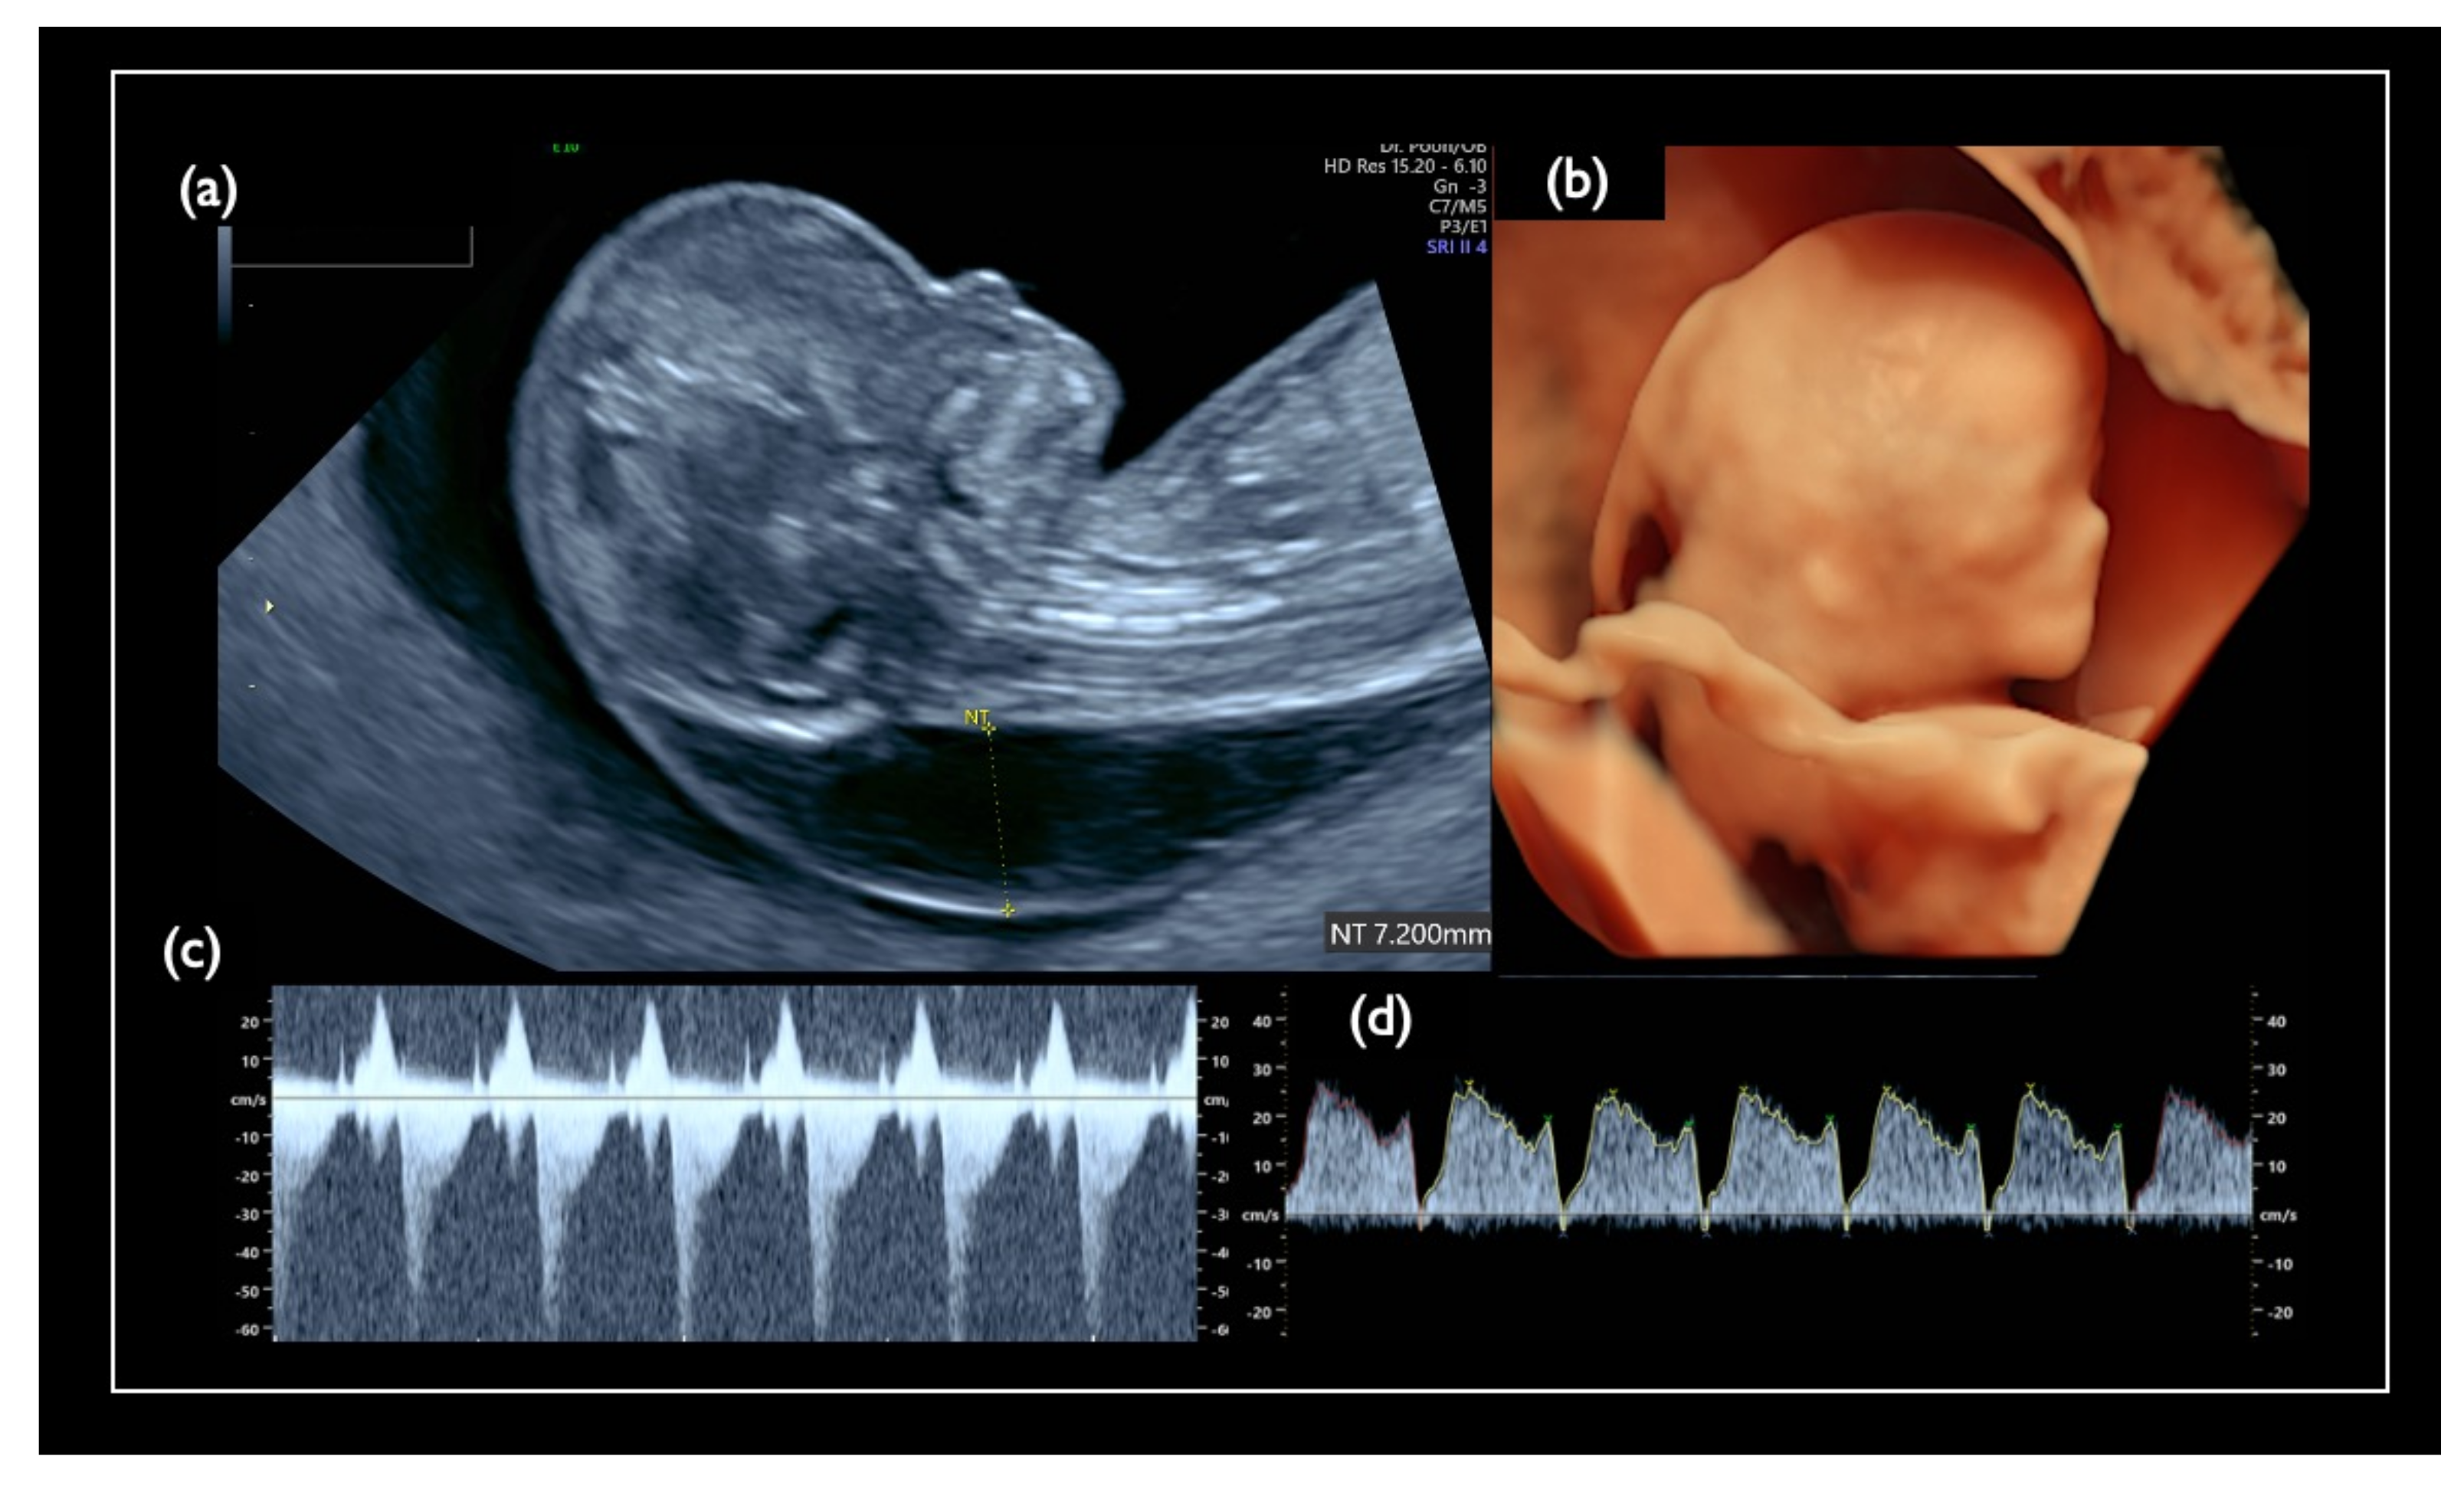

| FN1 | 47,XY,+21 | T21 negative | 1.07 | – | – | – | – | – | – | – | – | 46,XX | unclear | + | 7.2 | Increased NT, GE mild, NB defect, Lowset ear, TR mild, Small stomach, DV reverse, Tachycardia, T21 is strongly suspected |